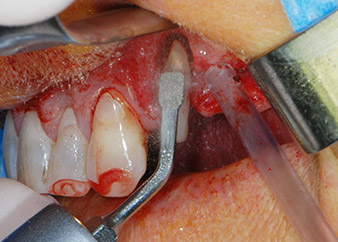

Un mois plus tard, le jour de l'intervention, la douleur et l'inflammation sur la dent 24 étaient minimes mais une mobilité de classe 2 de Miller était toujours observable. Après ouverture des lambeaux et nettoyage des tissus périapicaux et périradiculaires infectés, l'étendue du défaut osseux est devenue parfaitement visible (Figures 2 et 3).

À la racine de la dent, il manquait la totalité de l'os vestibulaire et distal. L'attache était essentiellement limitée à la racine palatine, venant ainsi confirmer le pronostic défavorable initial. La dent 27 présentait également une attache horizontale réduite et une raréfaction apicale minime (cf. Fig. 1), sans symptômes cliniques.

perte totale d'os et d'attache

Fig. 2 et 3 : Après élévation des lambeaux, un mois après le retraitement endodontique et le démarrage du traitement parodontal global, la racine de la dent 24 présentait une perte totale d'os et d'attache.